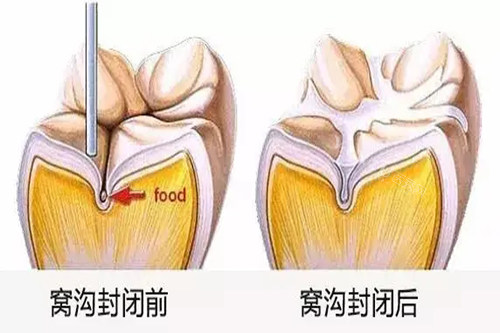

值得一提的是,这里提供从预防到治疗的全流程服务,包括定期涂氟、窝沟封闭等预防性措施,以及龋齿治疗、早期矫治等治疗项目。不少家长反馈,带孩子来这里不仅能解决现有问题,还能获得可靠的口腔保健指导。